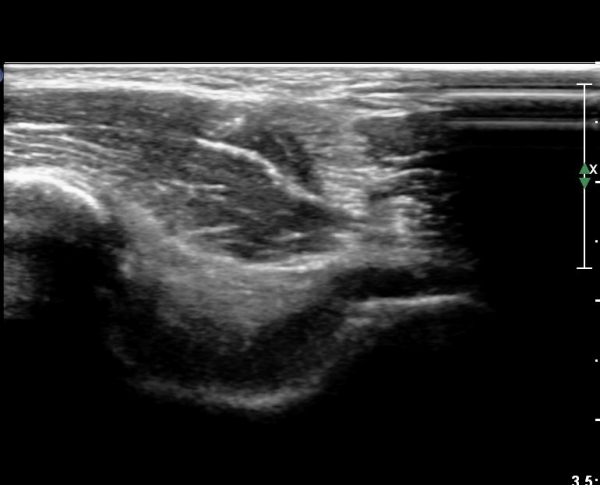

ÆÈ²ÞÄ¡ µÚÂÊ Á¾´Ü¸é°Ë»ç¿Í Ⱦ´Ü¸é°Ë»ç¿¡¼­ ÁֵοÍ(olecranon fossa)¿¡ ¼ö¾×Àú·ù°¡ °üÂûµÊ(»çÁø 1, 2)